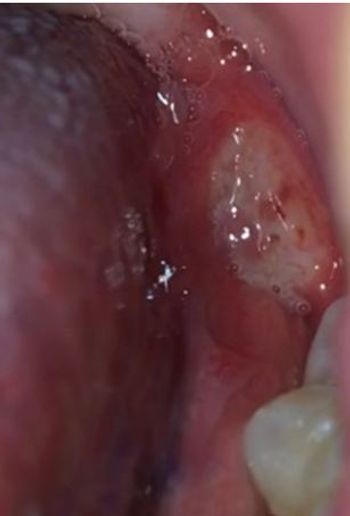

A 32-year-old man arrives at the ED unable to walk after jumping from a wall. This foot injury is often missed on x-ray. Do you see it?

Missed fractures of the foot are not uncommon. Examine the lateral x-ray view of this injury carefully to understand why.